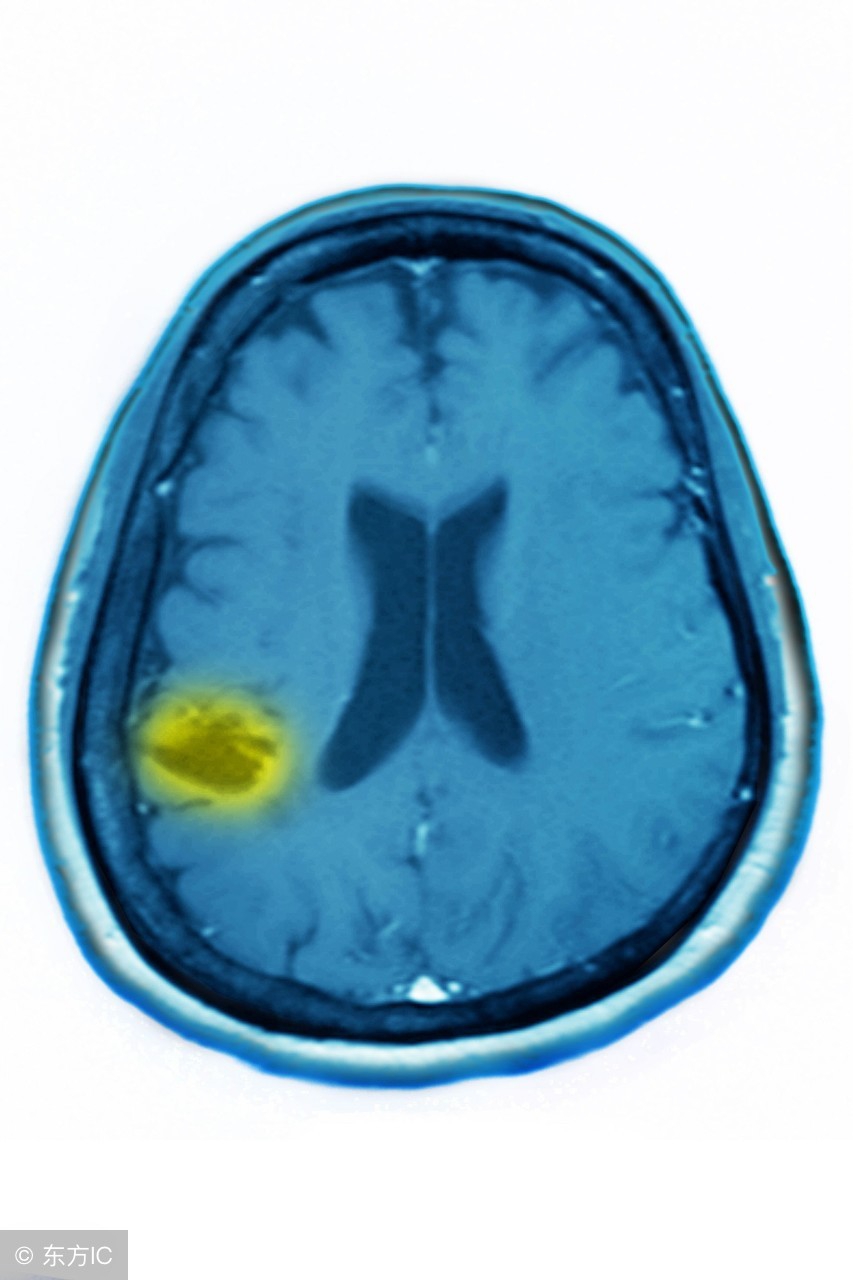

5、外伤也常是脑萎缩的诱发因素:慢性硬膜下血肿、脑挫裂伤、颅脑手术后遗症。

7、血管性疾病,如脑动脉硬化、脑供血不足、脑梗塞、脑溢血等都是脑萎缩的诱发因素。